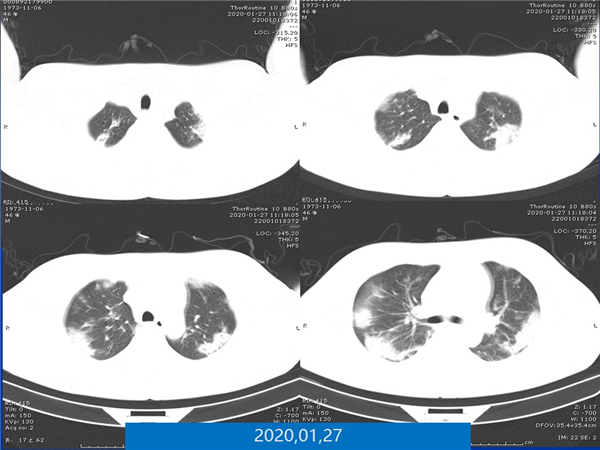

【病例分享】新型冠狀病毒感染肺部CT影像4例(常德市第一人民醫(yī)院)

幻燈片7.jpg